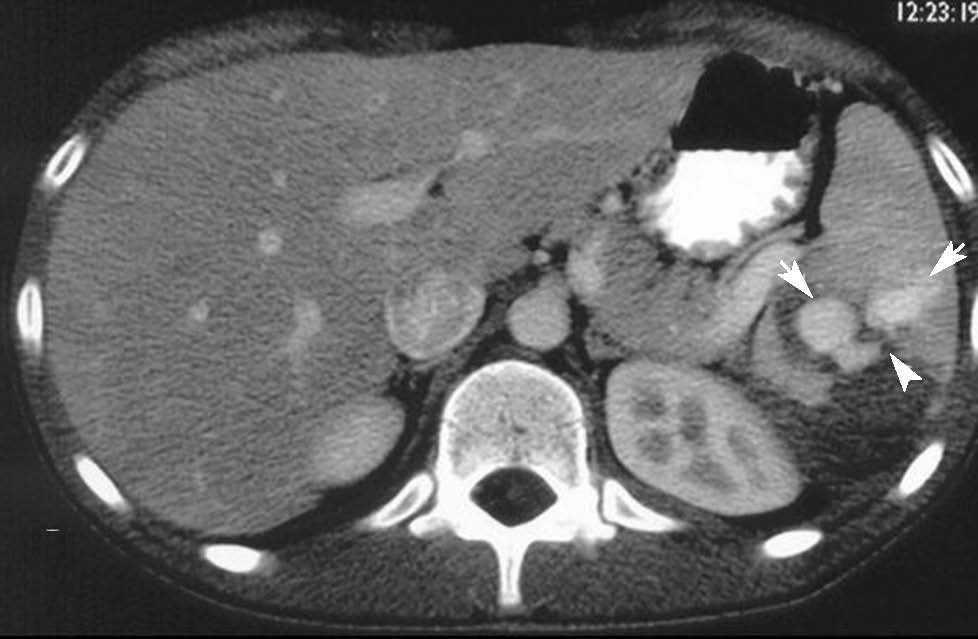

Paciente varón de 16 años que, tras experimentar un accidente de moto, fue atendido por un dolor abdominal. La analítica demostró una disminución del hematocrito en un 35%. La tomografía computarizada (TC) en la primera hora del ingreso mostró una laceración esplénica y hemoperitoneo en cantidad moderada. La TC de control realizada a los 3 días reveló la presencia de contraste extravascular contenido en la lesión esplénica (cabezas de flecha en fig. 1), por lo que se estableció el diagnóstico de seudoaneurisma intraesplénico. En arteriografía se confirmó la presencia de un trayecto de depósito de contraste extravascular dependiente de una rama intraesplénica de la arteria esplénica (flechas en fig. 2), que fue selectivamente embolizada con éxito. El paciente evolucionó de manera adecuada y fue dado de alta sin complicaciones.